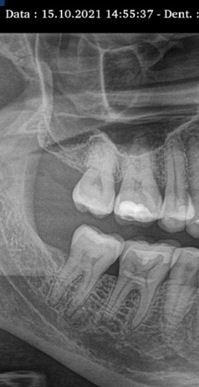

Quase dois anos após sua primeira visita, o paciente retornou à clínica relatando uma alteração notada em uma das lentes de contato dental, especialmente próxima à gengiva. Ao investigarmos, identificamos a presença de uma fístula e realizamos um rastreamento com radiografias (RX). Para nossa surpresa, constatamos a ausência de osso entre as raízes, evidenciando uma drenagem de pus. O paciente, curiosamente, não apresentava dor e o canal não havia sido tratado.

Ao revisarmos o exame inicial de 2021, verificamos que essa lesão não estava presente na primeira consulta. Em um período de quase dois anos, o paciente perdeu um dente devido a fatores como trauma, apertamento dental e a influência da Disfunção Temporomandibular (DTM). Este desfecho é lamentável, destacando que, mesmo para aqueles que mantêm dentes esteticamente atraentes, realizam tratamentos regulares e não aparentam problemas, a DTM pode se manifestar silenciosamente, resultando na perda dentária se a causa subjacente não for devidamente tratada. Este caso sublinha a importância de abordagens abrangentes e preventivas na odontologia, especialmente quando ligadas a condições como o estresse e o apertamento dos dentes.